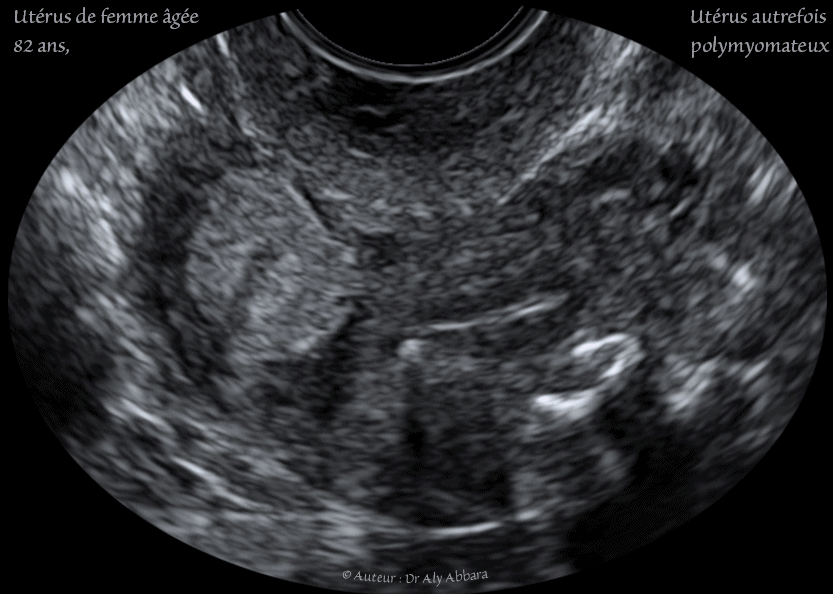

Utérus - femme de 82 ans - atrophie de l'endomètre - myomes involués - رحم إمرأة مسنة - ضمور بطانة الرحم - أورام ليفية ضامرة

Images échographiques animées montrant l'utérus d'une femme âgée de de 82 ans, avec plusieurs petits myomes utérins involués, calcifiés, intra-muraux, puis une atrophie de l'endomètre liée à l'effondrement du taux des estrogènes par l'inactivité de la fonction hormonale ovarienne.

رحم إمرأة مسنة بعمر 82 سنة : نلاحظ وجود ضمور بطانة الرحم بسبب القصور الهرموني المبيضي المرتبط بالعمر ؛ وجود أورامٍ ليفية رحمية متعددة وضامرة